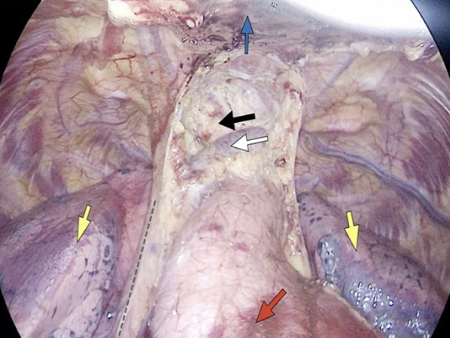

我院胸外科近日独立完成市域首例胸骨拉钩辅助剑突下单孔胸腔镜全胸腺切除术。该手术为纵隔疾病患者提供了更微创的治疗选择。

患者为高龄、伴有多种基础疾病的胸腺肿瘤患者。胸外科科主任刘浩带领刘斌手术团队经术前讨论,决定采用创伤更小的剑突下单孔入路,仅经一处约3cm的小切口,借助胸骨拉钩系统顺利完成全胸腺及病变组织的切除,术中出血少,过程顺利。患者术后恢复良好,次日即可下床活动,3天后出院。

传统胸腺切除术常需胸骨正中劈开或侧胸壁开胸,创伤较大,术后疼痛明显,恢复周期长。剑突下单孔胸腔镜全胸腺切除术在此基础上进行了重要改进,结合胸骨拉钩辅助,主要优势包括:

创伤小:仅一处约3cm切口,不切断胸骨或胸壁肌肉,更好保持胸廓完整性;

视野清晰:胸骨拉钩系统可提升胸骨后操作空间,提供稳定手术视野;

恢复快:术中出血少、组织干扰轻,术后疼痛较轻,住院时间缩短,并发症减少;

切口隐蔽:位于剑突下,疤痕小,兼顾美观。